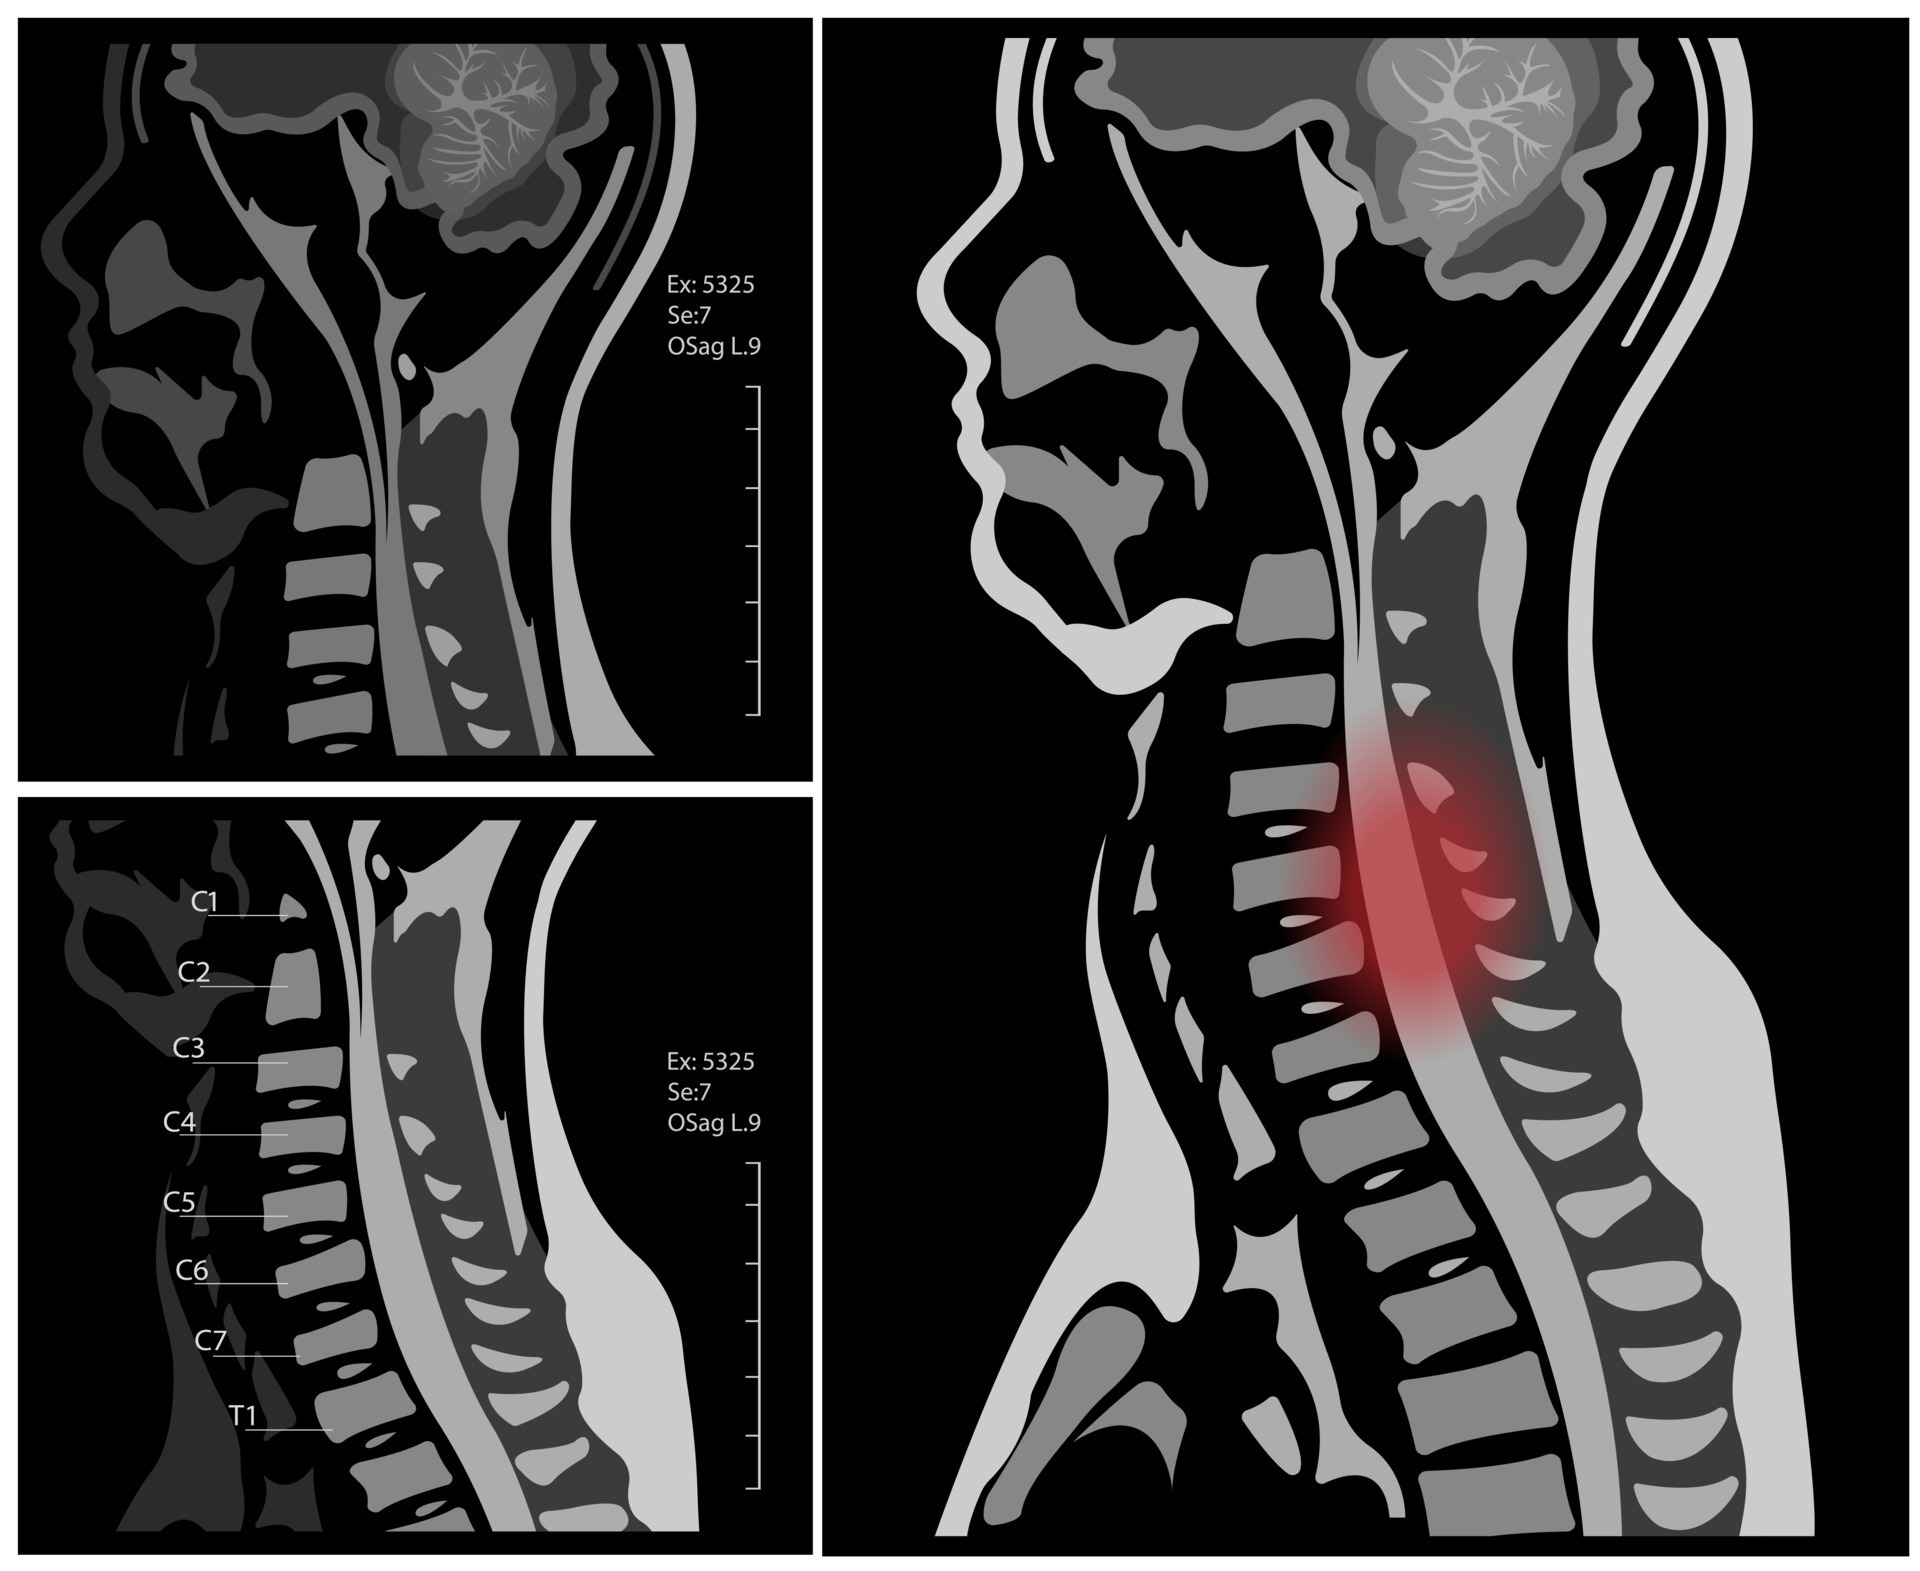

From www.vecteezy.com

MRI of the cervical spine with and without contrast, MRI with bilateral What Is A Cervical Mri Without Contrast A cervical mri (magnetic resonance imaging) scan uses energy from strong magnets to create pictures of the part of the spine that runs. For patients with known allergies to contrast material or those with compromised kidney function, mri without contrast becomes a safer alternative. A cervical mri scan is a medical imaging test that generates pictures of the cervical, or. What Is A Cervical Mri Without Contrast.